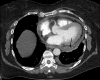

Figure 1. CTA chest with mild to moderate sized pericardial effusion

CTA: computed tomography angiography